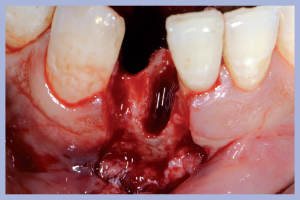

Procediamo all’estrazione degli elementi dentari 4.1 e 4.2 da cui residua un’importante deiscenza dei tessuti molli linguali. Notiamo inoltre come le estrazioni evidenzino uno spazio interdentale residuo anomalo con ampiezza al terzo incisale minore rispetto alla stessa al terzo cervicale. I suddetti due particolari rappresentano i punti focali di questo trattamento (Fig. 2).

- Fig. 2

- Fig. 2a

- Fig. 2b

- Fig. 2c